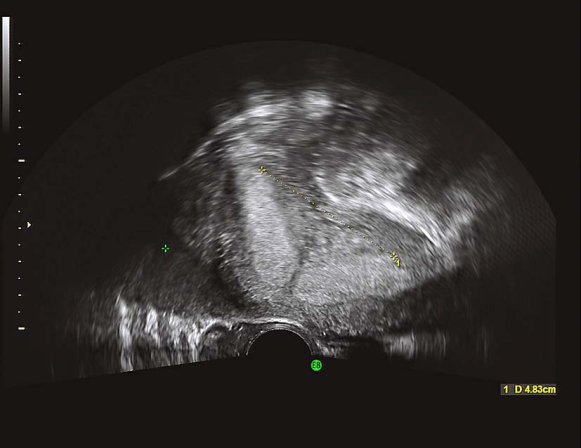

双角子宫二维超声

双角子宫三维超声

双角子宫二维超声碘油造影

(五)双角子宫(bicornuate uterus)

根据宫角在宫底水平融合不全的程度分为完全双角子宫和不全双角子宫。一般无症状。有时双角子宫月经量较多并伴有程度不等的痛经。检查可扪及宫底部有凹陷。超声检查、磁共振显像和子宫输卵管碘油造影有助于诊断。一般不予处理。若双角子宫出现反复流产时,可行子宫整形术。